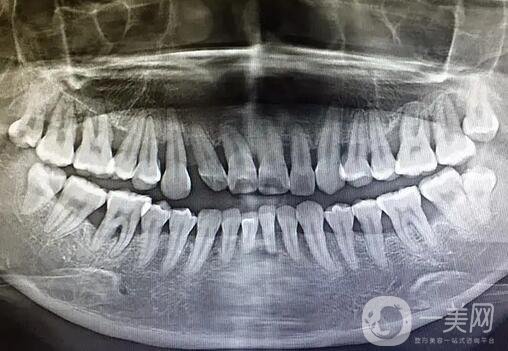

牙槽骨修整術(shù)是口腔外科常見的門診手術(shù)。其目的是去除阻礙義齒修復(fù)的部分,使牙槽嵴均勻承受咬合壓力,從而恢復(fù)咀嚼、語言、五官等口腔頜面功能。由于手術(shù)對象多為老年求美者,因此更應(yīng)重視術(shù)前心理護理、術(shù)中密切配合及術(shù)后教育。

牙槽骨修整術(shù)的適應(yīng)癥

1.義齒基托下方牙槽嵴突出嚴重;

2.拔牙后牙槽骨吸收不充分,留下尖銳的骨緣或膨出;

3.上下頜間隙過小,義齒難以戴上;

4.前牙牙槽骨過度突出,妨礙義齒建立正常牙齒,有礙美觀;

5.對于義齒修復(fù)者,拔牙后應(yīng)同時修整牙槽嵴,使其平整自然。